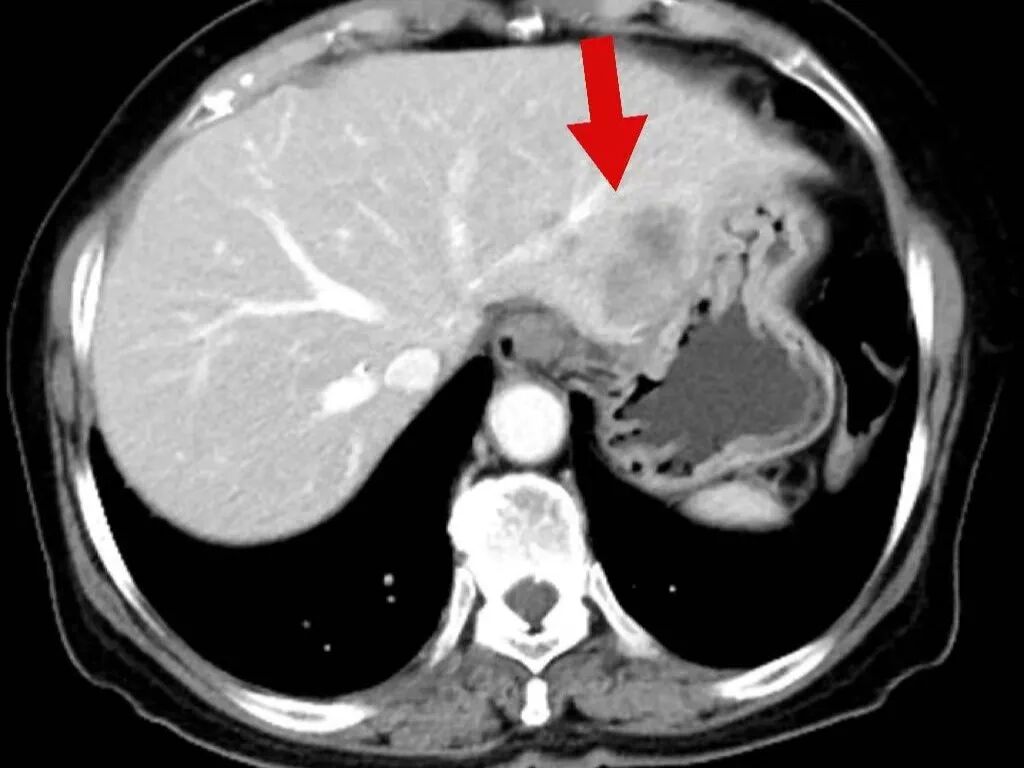

2025年3月17日,肿瘤诊疗中心团队首次为毕女士成功实施BACE治疗。术后患者病情暂时稳定,但5月10日复查显示肺部原发病灶稳定,肝脏转移病灶再次增大。

面对病情反复,团队没有放弃,果断升级治疗方案,决定同期施行BACE联合肝动脉化疗栓塞术,继续强化局部控制。“对于这类晚期患者,局部介入的优势在于能够高效、低毒地控制关键病灶。”介入医学科主任杨亚平说,“BACE联合肝动脉栓塞这类技术既能提高肿瘤部位的药物浓度,又减少了全身副作用,为后续治疗创造了条件。”

令人鼓舞的是,治疗一个月后复查显示,毕女士肺部和肝脏的肿瘤明显缩小,病情得到有效控制,生活质量显著改善。出院时,毕女士激动地说:“本来以为病情已经没希望了,是中山医院的专家们没放弃我,一次次调整方案,现在我不仅不怎么难受了,还能正常生活,真的太感谢他们了!

在玉溪市中山医院肿瘤诊疗中心治疗后,肿瘤在明显缩小